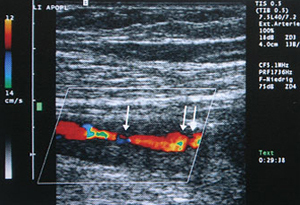

Ultraschallbild (Duplexsonographie):

normale Halsschlagader